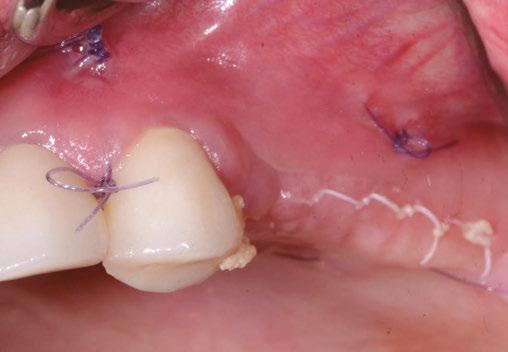

Building on the basics

Let’s review a recent case that showcases the rationale and techniques of the top three. It is common to utilize several suturing techniques in surgical closure, especially in larger grafting cases. In the following case, a lateral sinus lift was performed, and all three techniques were used to their full effect. Simple interrupted sutures are used to close small incisions and place tissue margins accurately back in place; horizontal mattress sutures are used to hold membranes in place and relieve tension over the incision line, and running interlocking continuous sutures are used to close longer incisions with watertight closure for maximum healing potential via primary closure.

A patient presented with a failing bridge on the upper left that is supported by three mini implants. The implants directly perforate the sinus and only ~2mm of residual bone height remains on the crest (Figure 8). The mini implants were removed, and a

Figures 7A and 7B: Horizontal mattress sutures are useful for helping to secure membranes in grafting situations and relieving tension in longer span incisions Figures 8A and 8B: The pre-op condition of the patient with mini implants engaging minimal bone and perforating the sinus. The patient’s implant supported bridge was loose and causing discomfort Figure 9: A periosteal biting mattress engages only the periosteum in the buccal vestibule and exit and re-enters on the lingual tissue, helping to secure the membrane tightly over the window and crest

Figure 10: Simple interrupted, papilla sling, and horizontal mattresses can be seen to achieve primary closure without any sutures over the main body of the incision. Passive closure requires that closure is obtainable without tension directly over the incision line, as seen here